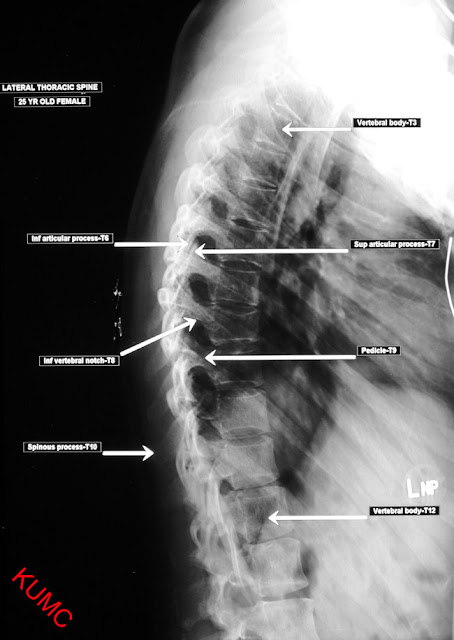

The chest x-ray is the most commonly performed diagnostic x-ray examination. A chest x-ray makes images of the heart,lungs, airways, blood vessels and the bones of the spine and chest.

anatomy of chest